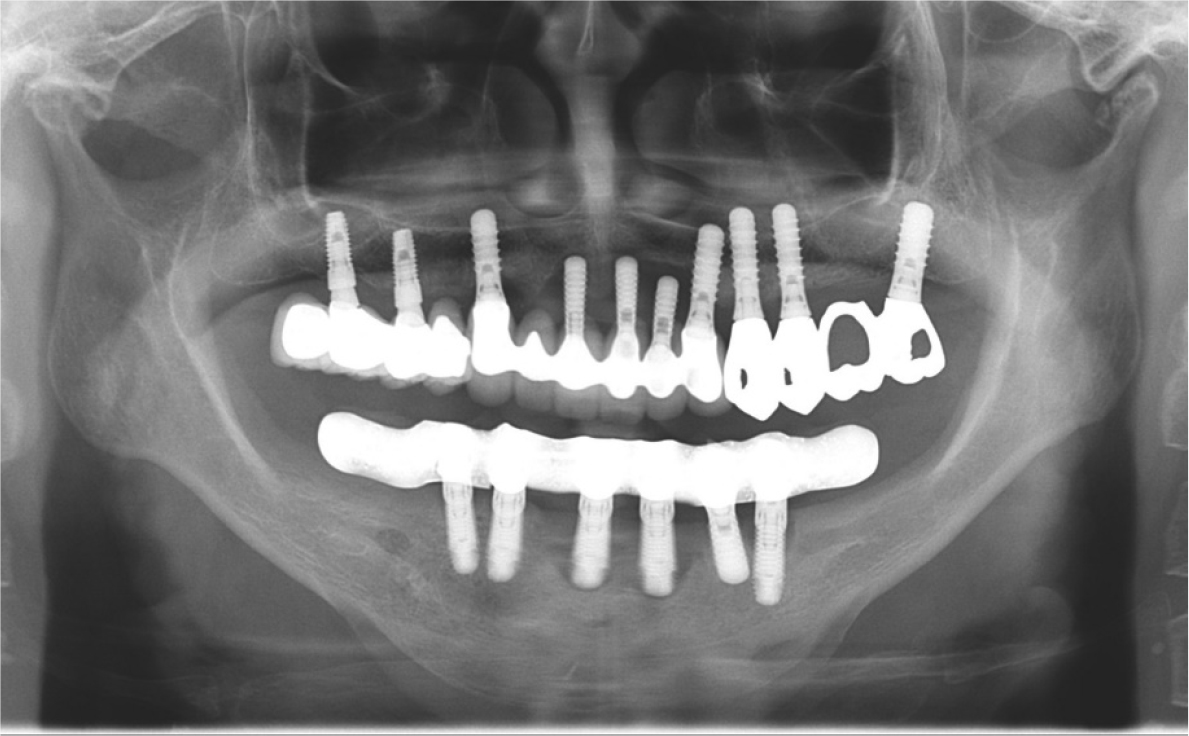

A 78-year-old female patient presented with gingival swelling and pain in the anterior arch. The patient mentioned that the implant-supported FDP was set up approximately 15 years ago in a local dental clinic (Figs. 1 and 2).

Clinical and radiographic examinations revealed bone resorption and inflammation around the implants in the maxilla and mandible, and the implant threads were exposed in the oral cavity (Fig. 3). The implants in #11, 21, 22, 31, and 41 areas (Brånemark System Mk II TiUnite; Nobel Biocare AB, Göteborg, Sweden) were diagnosed as failing because of osteomyelitis caused by MRONJ. The patient had been receiving alendronate-based drugs for osteoporosis since 2015. Meanwhile, no critical biological concern was found in other implants, except for mild peri-implantitis. The treatment modalities were explained to the patient, and implant-supported double-crown-retained removable dentures were chosen for the mandible.

The FDP in the anterior area of the maxilla and the full-arch FDP in the mandible were removed, and the hopeless implants were removed under local anesthesia. After three months of healing (Fig. 4), when the gingiva and underlying bone stabilized, prosthetic treatment commenced. a six-unit metal ceramic FDP was fabricated in the maxilla using conventional silicone impression and casting procedures. In the mandible, pick-up impression taking was performed for the four remaining implants using an individual tray and silicone materials (Aquasil Ultra LV; Dentsply Sinora, Philadelphia, PA, USA) (Fig. 5). Inner crowns with a 2° convergence angle and a chamfer margin were fabricated for the four implant fixtures with Co-Cr alloy (VeraBond 2V; Aalbadent, Fairfield, CT, USA) (Fig. 6). The corresponding outer crowns were fabricated and attached to the metal framework of the denture using a laser welding technique. Afterwards, fabric pins with the diameter of 0.8 mm were placed on the outer crowns using the spark erosion technique. The vertical dimension of the occlusion was established considering esthetics and function. Artificial teeth (Endura; Shofu, Kyoto, Japan) were arranged using the group function concept and a wax denture was created (Fig. 7). After confirming the wax denture in the oral cavity, a definitive prosthesis was fabricated using flasking, wax wash, and resin packing procedures (Fig. 8).

Periodic recall checks were done every three months after the delivery of the definitive prosthesis. During the three year follow-up period, no periodontal or prosthetic complications were observed (Fig. 9). The patient was satisfied with the ease of hygienic care for the definitive prosthesis, and the implants were well maintained.